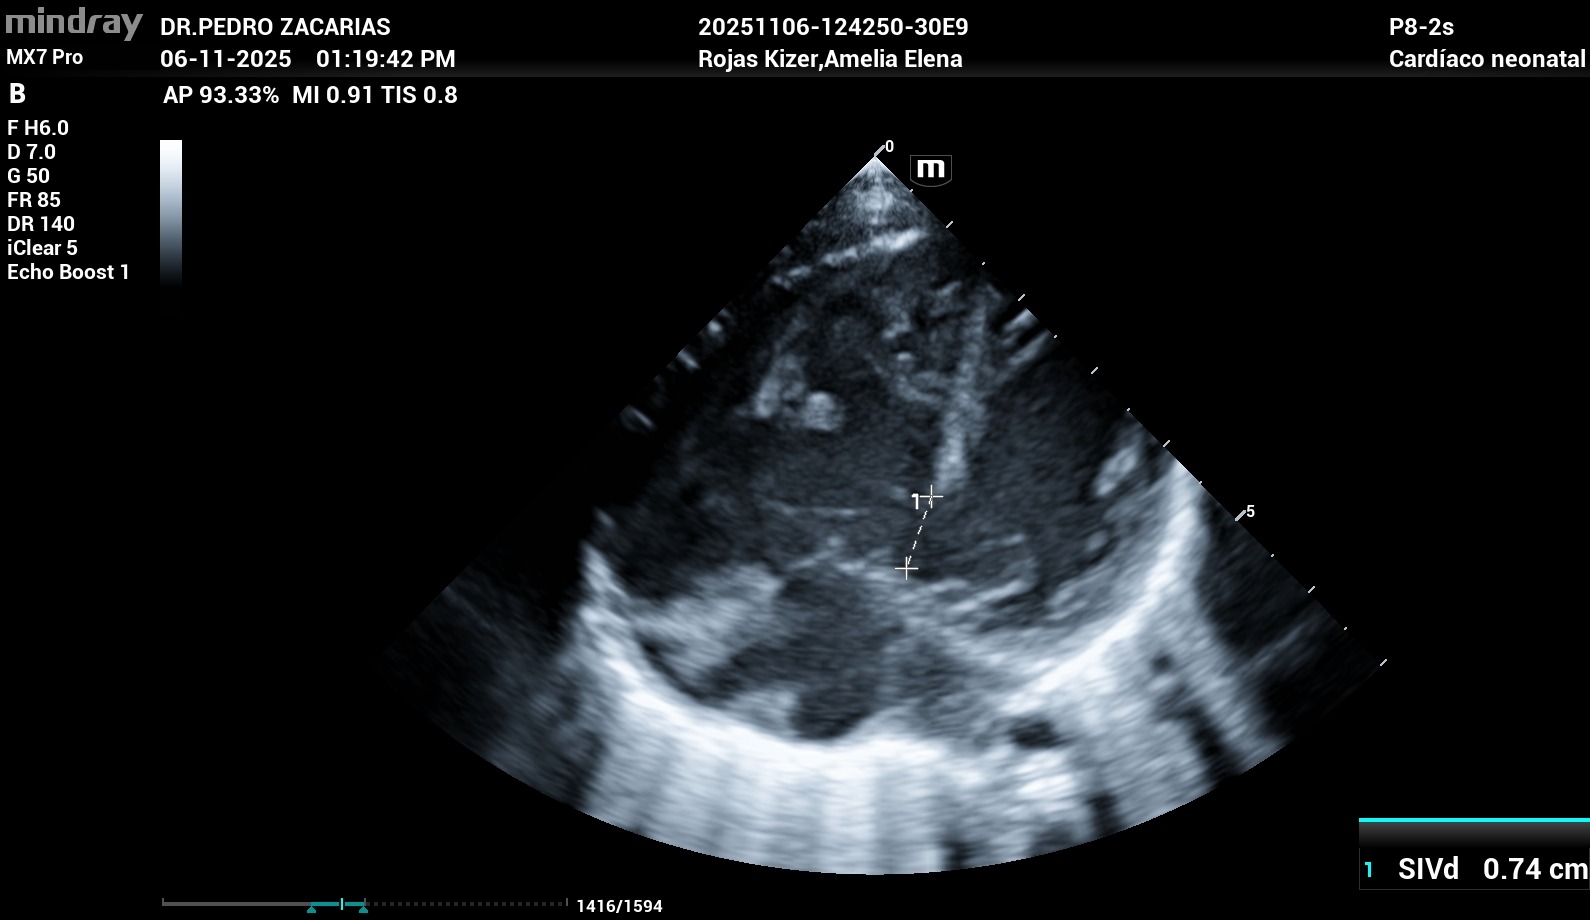

Al mes de nacida fue diagnosticada con una cardiopatía congénita compleja: Canal Auriculoventricular Completo Rastelli tipo A, además de otras malformaciones cardíacas como PCA, CIV y CIA. Estas condiciones hacen que su pequeño corazón no se haya formado correctamente y hoy tenga que trabajar el doble para mantenerla con vida.